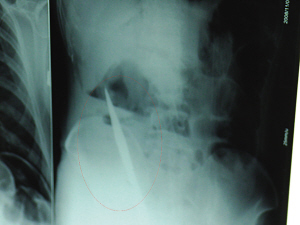

X光片上,尖刀清晰可見(jiàn)。

從男子體內(nèi)取出的尖刀足足有19厘米長(zhǎng)。

6日上午,記者在徐州礦務(wù)集團(tuán)總醫(yī)院重癥監(jiān)護(hù)室見(jiàn)到了這名男子,目前他雖然已經(jīng)恢復(fù)了意識(shí),但還不能開(kāi)口說(shuō)話(huà),需要呼吸機(jī)輔助呼吸。據(jù)醫(yī)生介紹,4日中午12時(shí)左右,這名男子因服毒輕生被緊急送到醫(yī)院進(jìn)行搶救,之前,這名男子已經(jīng)在當(dāng)?shù)剜l(xiāng)鎮(zhèn)醫(yī)院進(jìn)行了近20小時(shí)的治療,但效果不佳!安∪吮晦D(zhuǎn)院到礦總院時(shí)已神志不清,血壓極低,處于休克狀態(tài)。”救護(hù)人員給男子洗胃、初步處理以后,發(fā)現(xiàn)男子呼吸急促,于是趕緊給他拍片檢查。結(jié)果讓所有的醫(yī)生大吃一驚,竟有一把尖狀異物橫在該男子腹腔內(nèi)!當(dāng)天下午5時(shí)30分,輕生男子被推上了手術(shù)臺(tái)。經(jīng)過(guò)40多分鐘的手術(shù),該男子腹腔被打開(kāi),手術(shù)醫(yī)生發(fā)現(xiàn),男子體內(nèi)的金屬狀異物竟然是一把長(zhǎng)19厘米的尖刀!